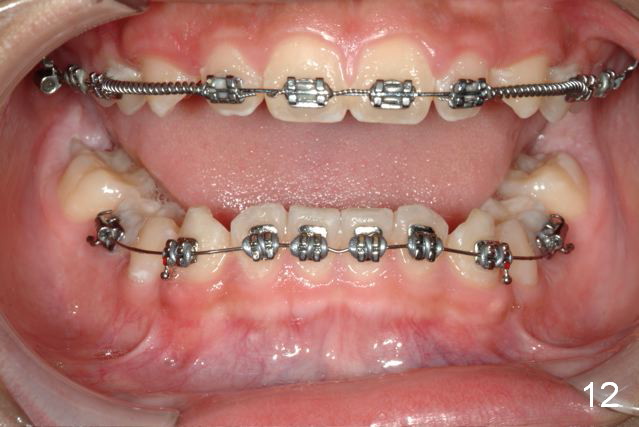

Brackets were placed on 2015_09_06 (Fig.11-13, Phase I pre-orthopedic tooth movement, leveling in advance of Herbst appliance therapy using ankylosed Es).   Six months later (Fig.14-16), LR7 did better, LL7 did not and will need intervention. But intrusion of L 3-3 looks good.